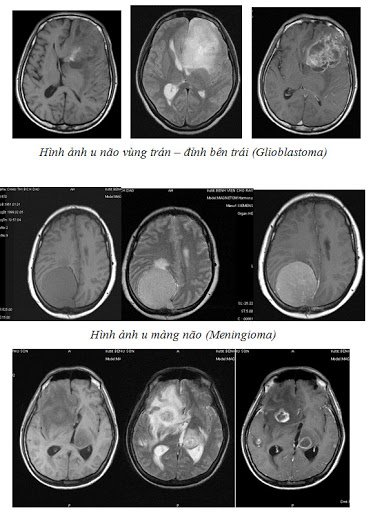

Chụp cộng hưởng từ Não và tủy sống nhằm xác định:

● Ung thư não, tủy sống hoặc những tổn thương tủy sống;